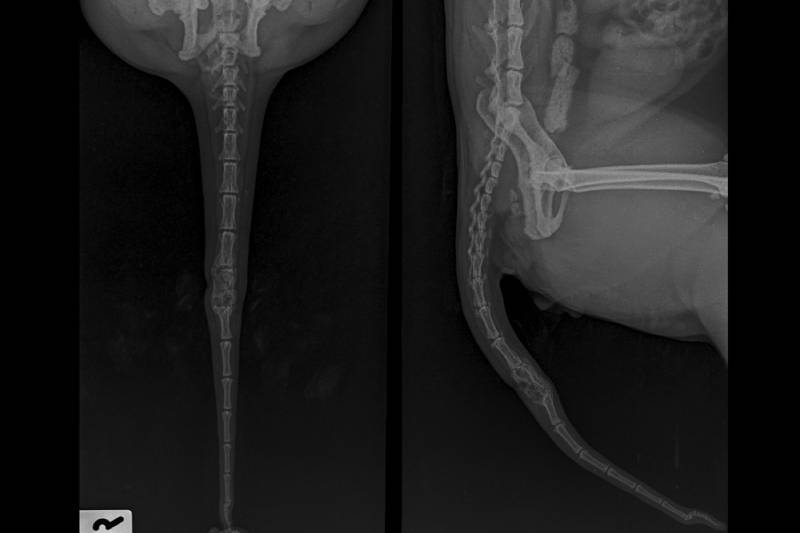

Your veterinarian will examine the tail and determine if x-rays are necessary. If there is also tearing of skin, you might have to administer medications or care for the wound as directed by your vet.

There are various kinds of tail damage. What might initially look like a break, also called a fracture, might be a sprain or dislocation. This is another reason why it is imperative to get to your vet immediately. Each injury requires different treatment, and some are more problematic than others.

Fractures/Breaks

Fractures and breaks occur when the bones are damaged, split, splintered, or crushed. This may happen in a road traffic accident or from being trapped. Typically fractures at the tip of the tail usually heal well without any surgical treatment. However, the more severe the break, the more involved the therapy. Again your veterinarian will advise you on medications and treatments required.